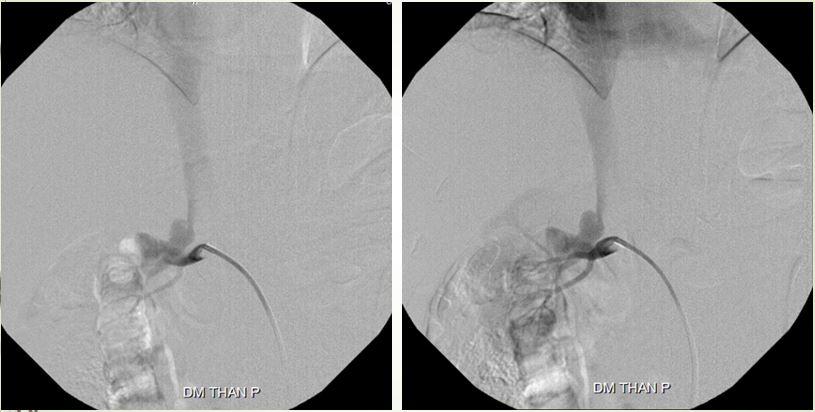

Ca lâm sàng thứ 2 là một bệnh nhân nam 63 tuổi, vào viện vì đau bụng, tiểu máu từng đợt… trước đó, ông đã đi khám từ Bắc chí Nam mà không nơi nào tìm ra hướng giải quyết cho tình trạng của mình. Tại bệnh viện, các bác sĩ đã tìm thấy nguyên nhân là bệnh nhân có rò động tĩnh mạch thận lưu lượng rất cao. Để khắc phục tình trạng này, BS Trần Chí Cường đã can thiệp, dùng bóng để giảm dòng chảy vào động mạch thận để có đường vào sâu hơn, bơm keo gây tắc vị trí thông động tĩnh mạch.

Kỹ thuật dùng bóng kiểm soát dòng chảy và bơm keo

Sau gây tắc bằng keo và bóng

Chỉ trong 24 giờ sau can thiệp, nước tiểu của bệnh nhân trong vắt, trở lại cuộc sống bình thường.